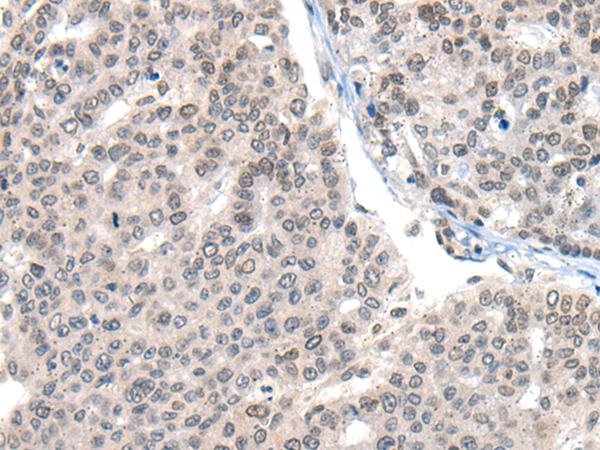

分类: 科研抗体货号: P13159别名: HNRPR; hnRNP-R应用: IHC反应种属: Human